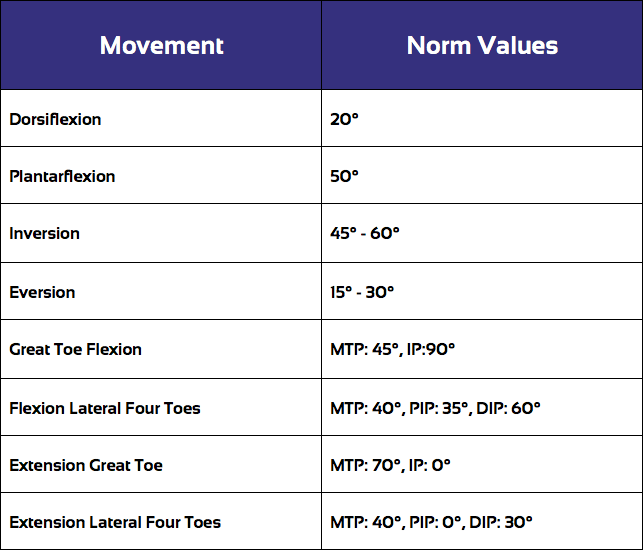

最好从主动活动范围评估开始:

不同方向运动范围的标准值如下:

AROM 评估之后通常会进行被动运动范围评估(PROM),您可以点击以下视频观看:

在 PROM 评估过程中,将受影响踝关节的活动范围和末端感觉与未受影响的一侧进行比较非常重要。